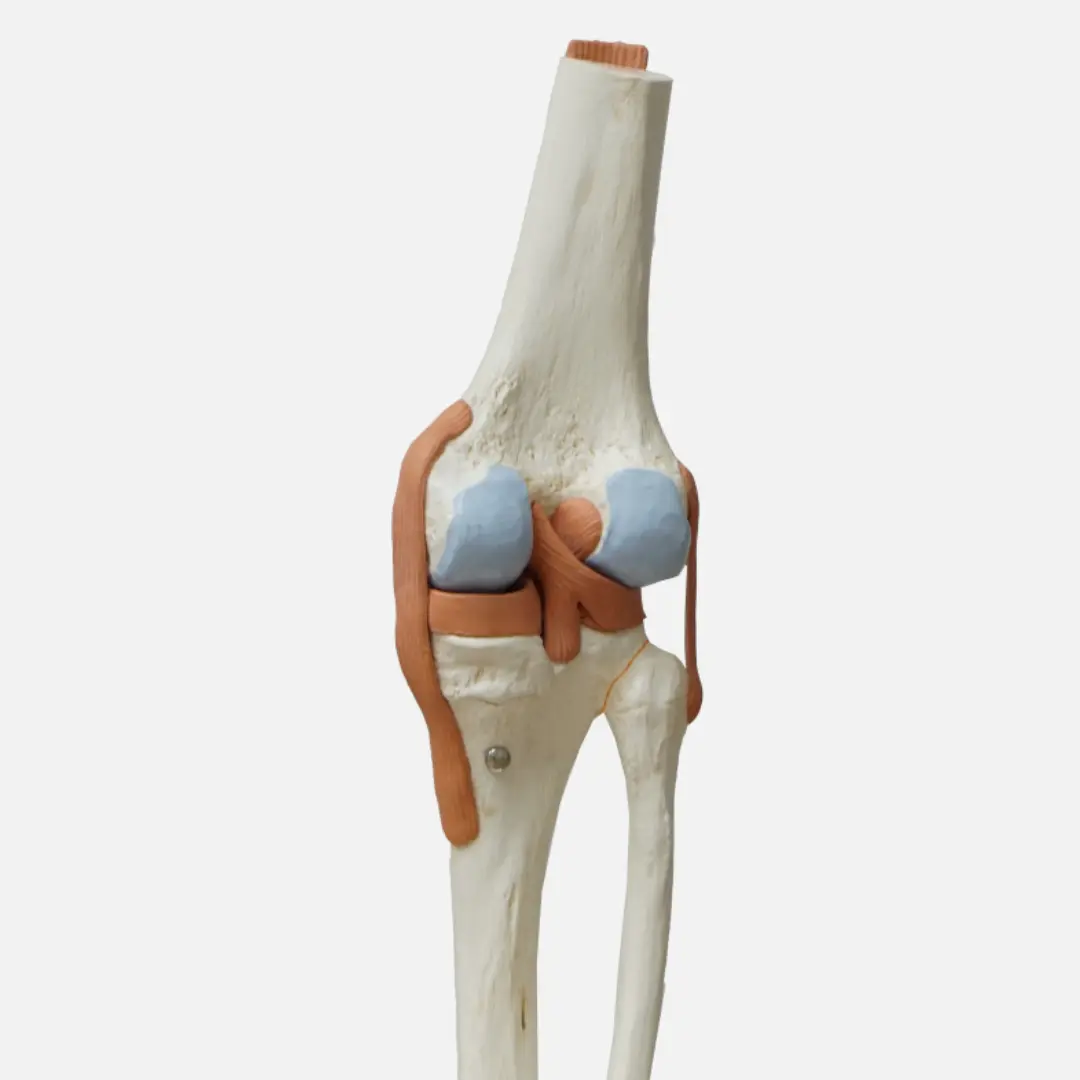

콘드로이친(Chondroitin)은 우리 몸의 연골, 인대, 힘줄, 피부 등 결합 조직에 풍부하게 존재하는 성분입니다. 특히 연골의 주요 구성 성분 중 하나인 프로테오글리칸을 구성하는 핵심 성분이죠. 연골은 관절의 충격을 흡수하고 뼈와 뼈 사이의 마찰을 줄여주는 쿠션 역할을 하는데, 이 연골의 탄력성과 수분 유지를 돕는 것이 바로 콘드로이친입니다.

- 수분 흡수 및 유지: 콘드로이친은 연골 내에 많은 양의 수분을 끌어당기고 유지하는 능력이 탁월해요. 이 덕분에 연골이 탱탱하고 탄력 있게 유지될 수 있습니다.

- 충격 흡수 능력 향상: 충분한 수분을 머금은 연골은 외부 충격에 더 효과적으로 대응하여 관절을 보호합니다.

- 연골이 튼튼해지면 관절의 쿠션 역할이 강화되어 외부 충격을 효과적으로 흡수하고 뼈와 뼈 사이의 마찰을 줄일 수 있습니다.